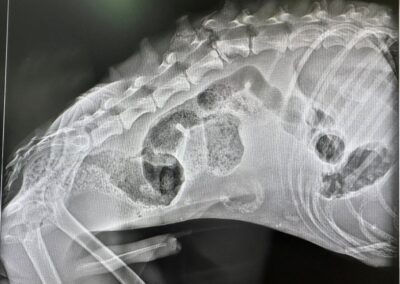

Mico (M) Hôpital / Refuge de Tobarra Jan 5Jan 5 association-LSF Je veux l'adopter Description Infos à venir TweetezPartagezPartagezÉpingle0 Partages